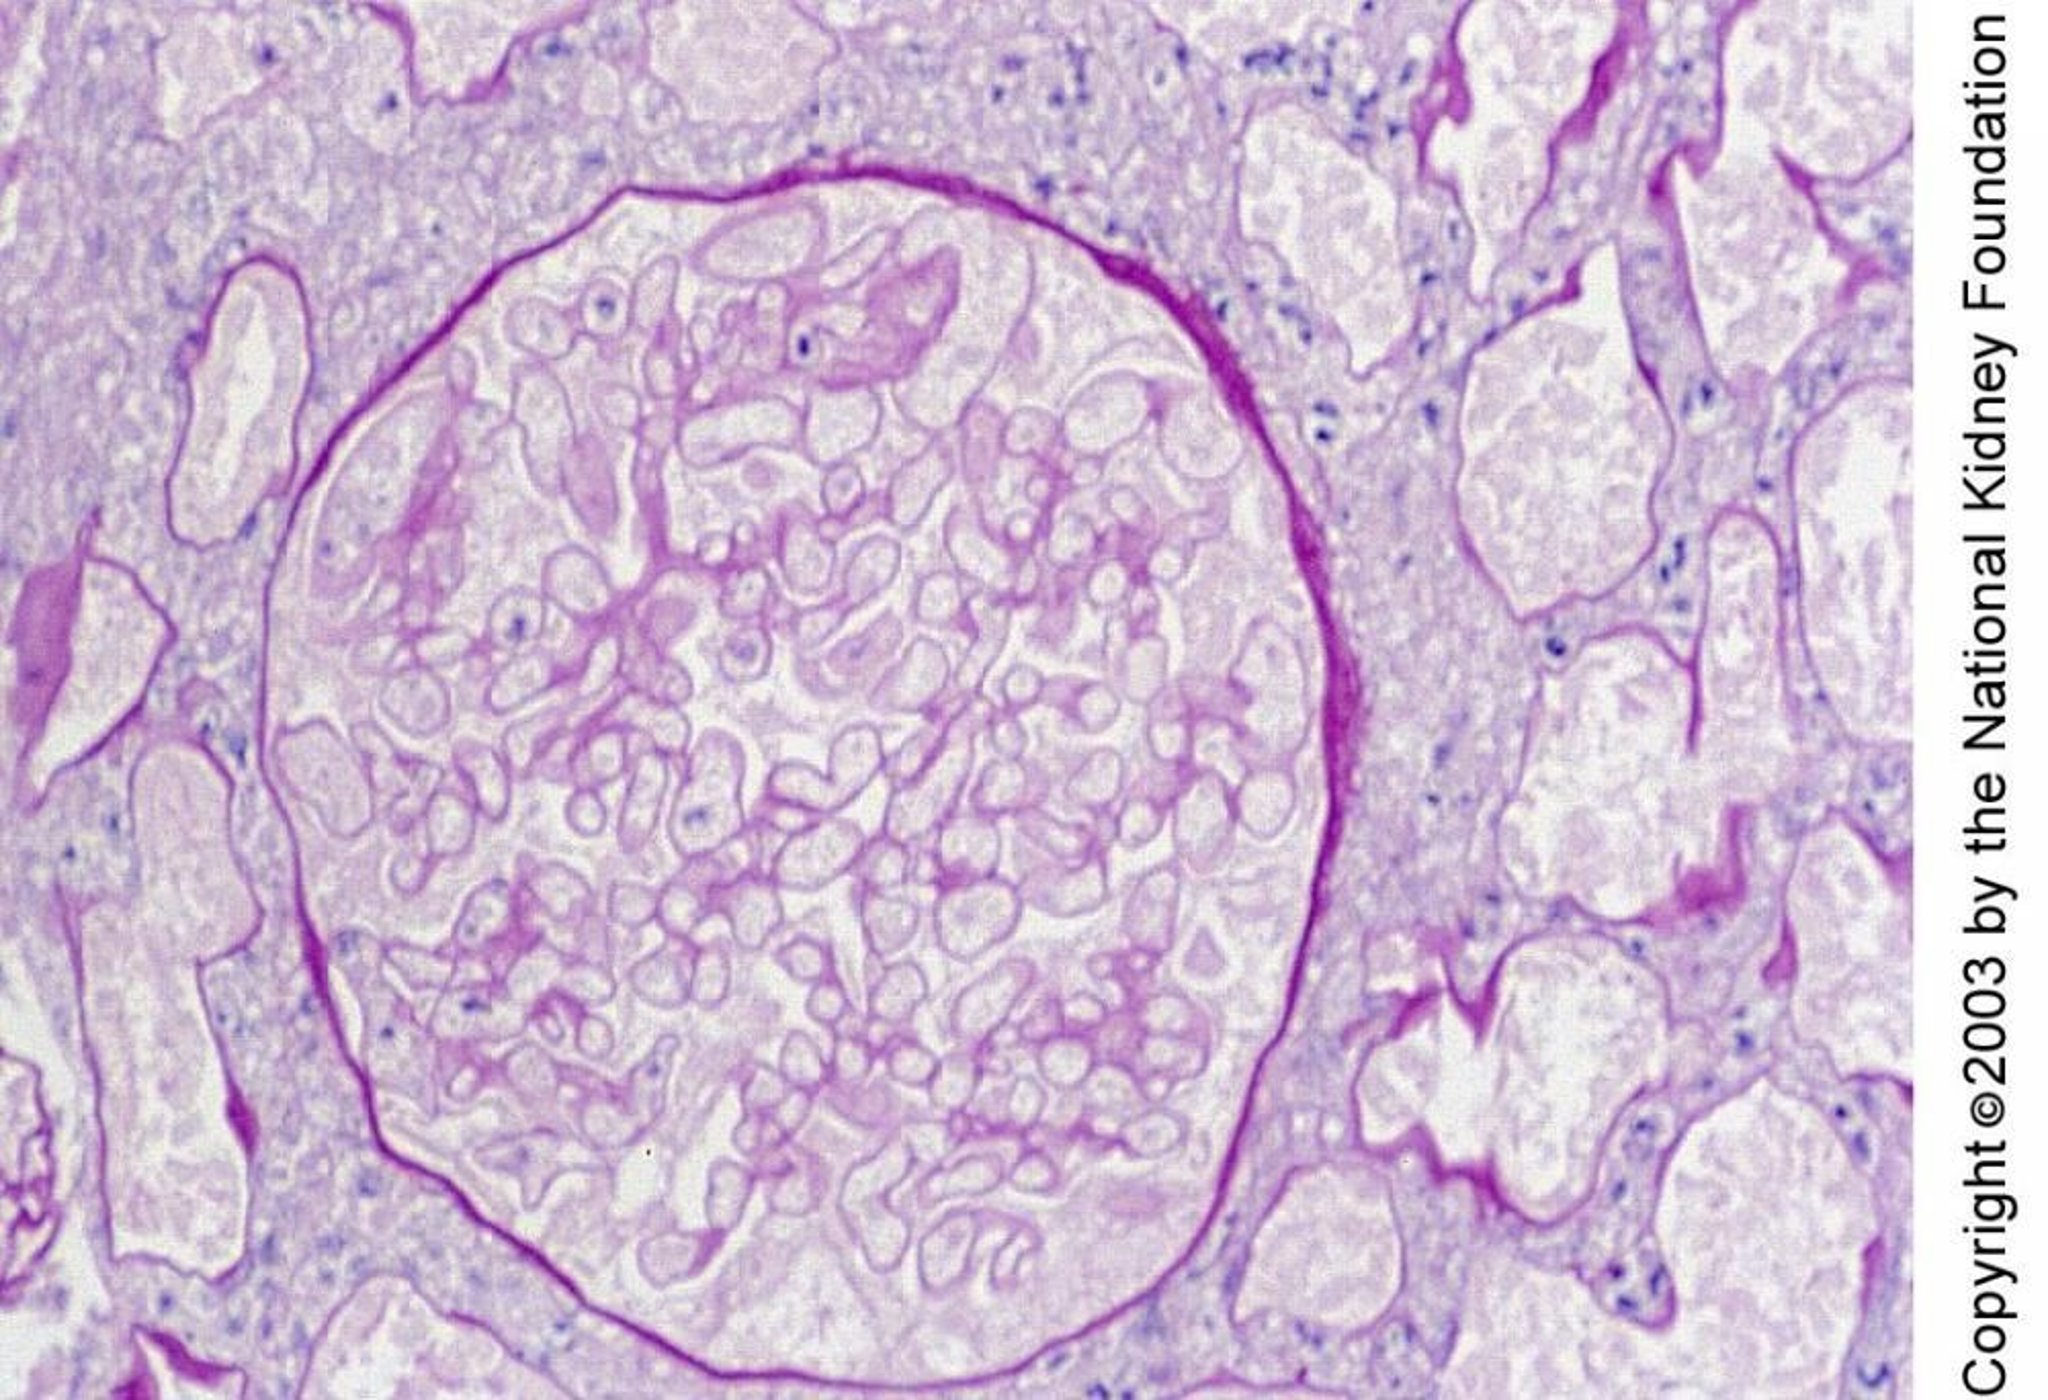

Nierenrindennekrose

Die Nekrose der Nierenrinde ist histologisch durch die Nekrose von Glomeruli und Tubuli gekennzeichnet. Die Nekrose in dieser Biopsieprobe zeigt sich durch kleine Zellkerne und geisterhafte Umrisse der Zellen (periodische Säure-Schiff-Färbung, ×400).

Image provided by Agnes Fogo, MD, and the American Journal of Kidney Diseases' Atlas of Renal Pathology (see www.ajkd.org).